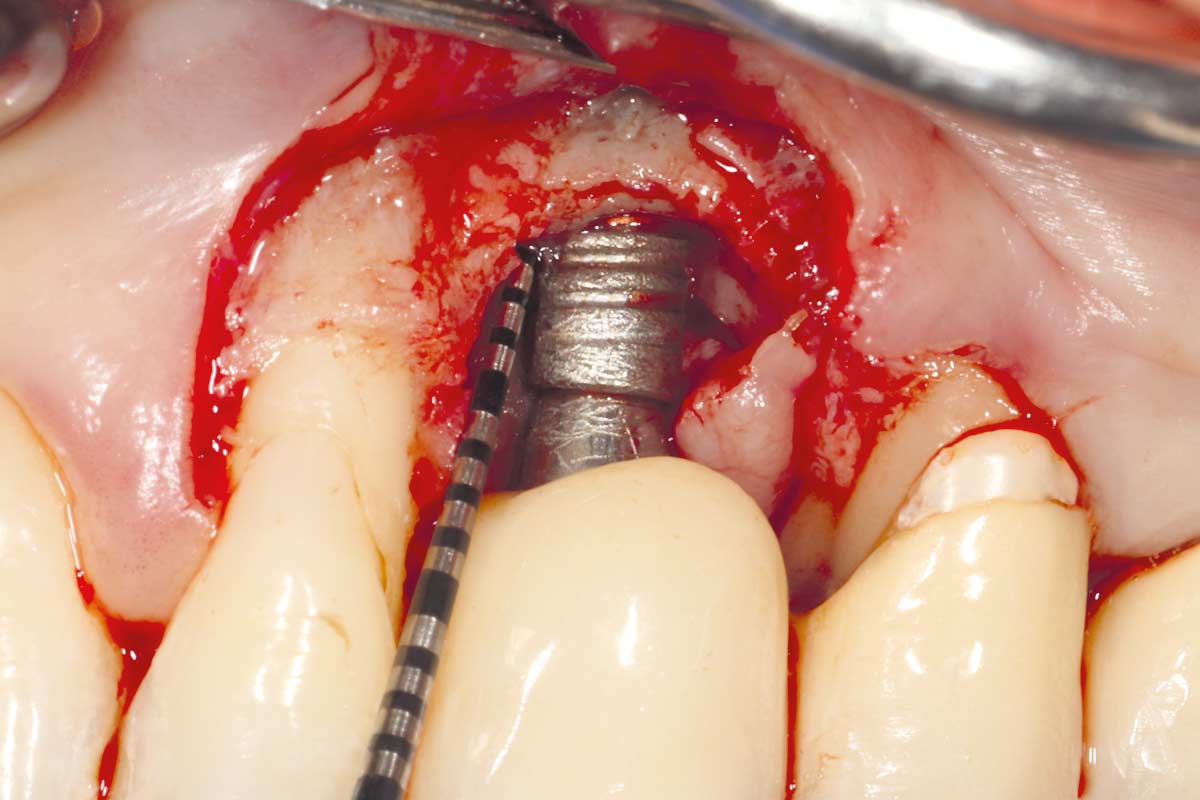

A patient presented with a peri-implant bone defect characterized by bone resorption compromising the stability and long-term prognosis of the implant. To re-establish sufficient bone volume and ensure implant longevity, a regenerative surgical intervention was performed using a guided bone regeneration (GBR) approach. The treatment featured cerabone® plus for grafting, complemented by the Shield Technique using fully resorbable magnesium-based NOVAMag® SHIELD to guide bone regeneration.